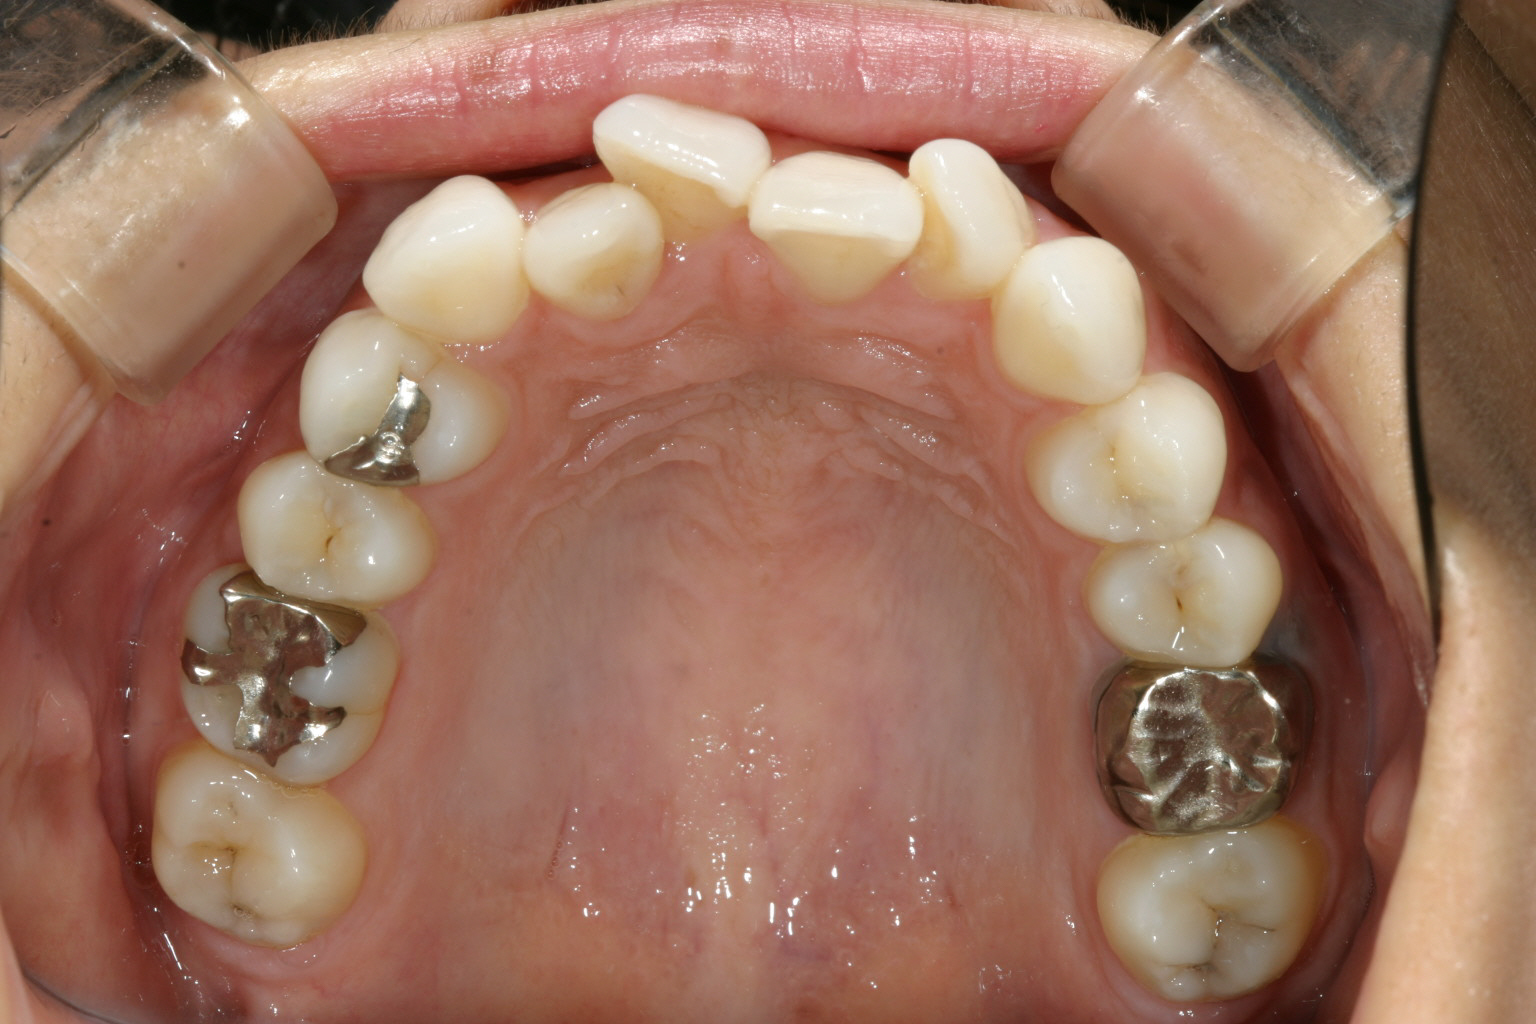

前歯がかなりグチャグチャしています。

下顎は上顎程では無いですが少し叢生になっています。